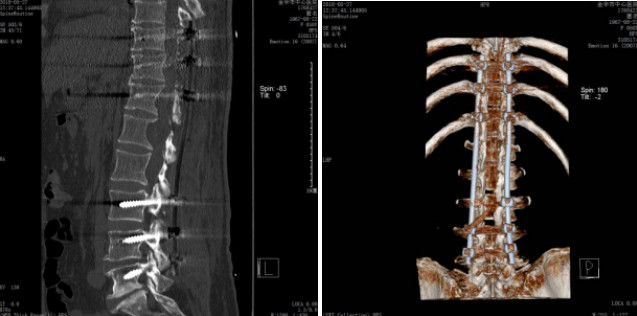

完善术前准备后, 2018年5月24日,在学科带头人袁坚列书记支持下、由周格知科主任主刀,范越君脊柱团队参与下开展了金华市中心医院神经外科这例节段最长的椎管内肿物手术,切口长约30cm,奋战15小时31分钟,切除10个椎体棘突,术中发现椎管内肿物突向椎管各个间隙生长,相互挤压、神经束移位,单纯摘除个别肿物根本不能缓解占位效应,遂在电生理监测下实施了最大程度的切除肿瘤:所有肿瘤尽量经包膜内切除,如黄豆大小肿瘤则经纤维束纵轴切开包膜后施行“娩出”,术中椎管内摘除大大小小肿瘤共计100余粒,并一期行双侧胸10、胸11、胸12、腰4、腰5及腰3右侧经椎弓钉棒内固定,术后复查影像学满意,内固定位置良好:

术后影像资料